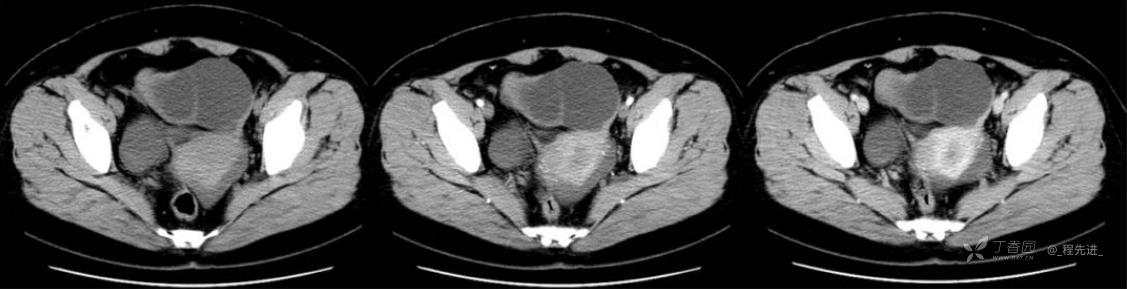

1月特别精彩病例|中老年女性,盆腔包块近半年持续增大【病理已公布】

患者年龄:53岁

简要病史:4年前体检时发现盆腔包块及子宫肌瘤,近半年复查盆腔彩超发现包块持续增大,近1年月经欠规律,伴腰、腹胀。

体格检查:宫颈举痛(+),子宫增大,质地中等,活动可,无压痛;右下腹轻压痛,无反跳痛,左侧附件区未扪及明显包块,无压痛。

阴式彩超:子宫约65*58*44mm大小,子宫肌层可见多个低回声块影,较大的为35*27mm(位于子宫前壁下段偏右侧壁),边界清,内回声欠均匀,后方回声衰减。考虑子宫多发肌瘤。子宫后壁可见一混合回声包块,大小约31*20mm,边界不清,内呈强弱回声,分布不均,考虑子宫腺肌瘤,其他疾患待删。子宫内膜厚6mm,宫颈可见多个囊性暗区,边界清,内透声好,后壁效应增强,较大的为15*11mm。子宫前方偏左侧可探及一大小89*75mm囊性肿块,边界清,壁薄光滑,内透声好,可见分隔光带